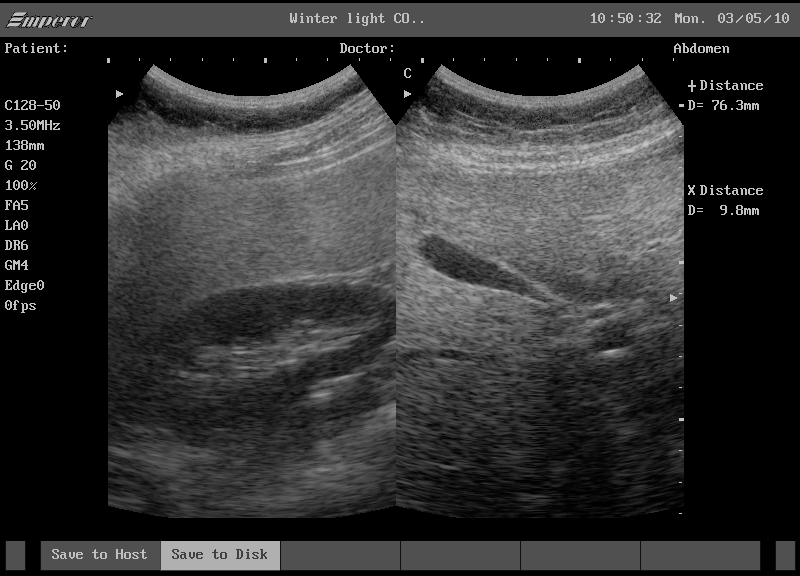

신장 결석, 신장근종, 신우신염 등 신장과 관련된 여러 질환 역시 복부 초음파 검사를 통해 진단됩니다. 신장초음파는 신장의 크기, 모양, 내부의 돌이나 혹을 확인하는 데 유용하며, 특히 건강검진 중 우연히 발견되는 경우가 많아 조기 발견 및 치료에 기여하고 있습니다.

종양이나 낭종 등 복부 내 다양한 이상 소견들도 초음파 검사를 통해 확인할 수 있습니다. 예를 들어, 건강검진 결과 우연히 발견되는 신장근종(11cm)과 같은 경우, 초음파 검사를 통해 종양의 위치와 크기, 경계 상태 등을 파악하여 추가 검사 및 치료 방향을 결정하게 됩니다.

한 예로, 건강검진 도중 복부 초음파 검사를 진행하던 중 우연히 신장근종(11cm)이 발견된 사례가 있습니다. 이 환자는 별다른 증상이 없었으나, 정기 검진을 통해 조기 발견이 가능했던 덕분에 이후의 치료 계획 수립에 큰 도움을 받았습니다. 또 다른 사례로는 복부 초음파 검사를 통해 담석증이 조기에 발견되어, 증상이 악화되기 전에 치료를 진행한 경우도 있습니다.